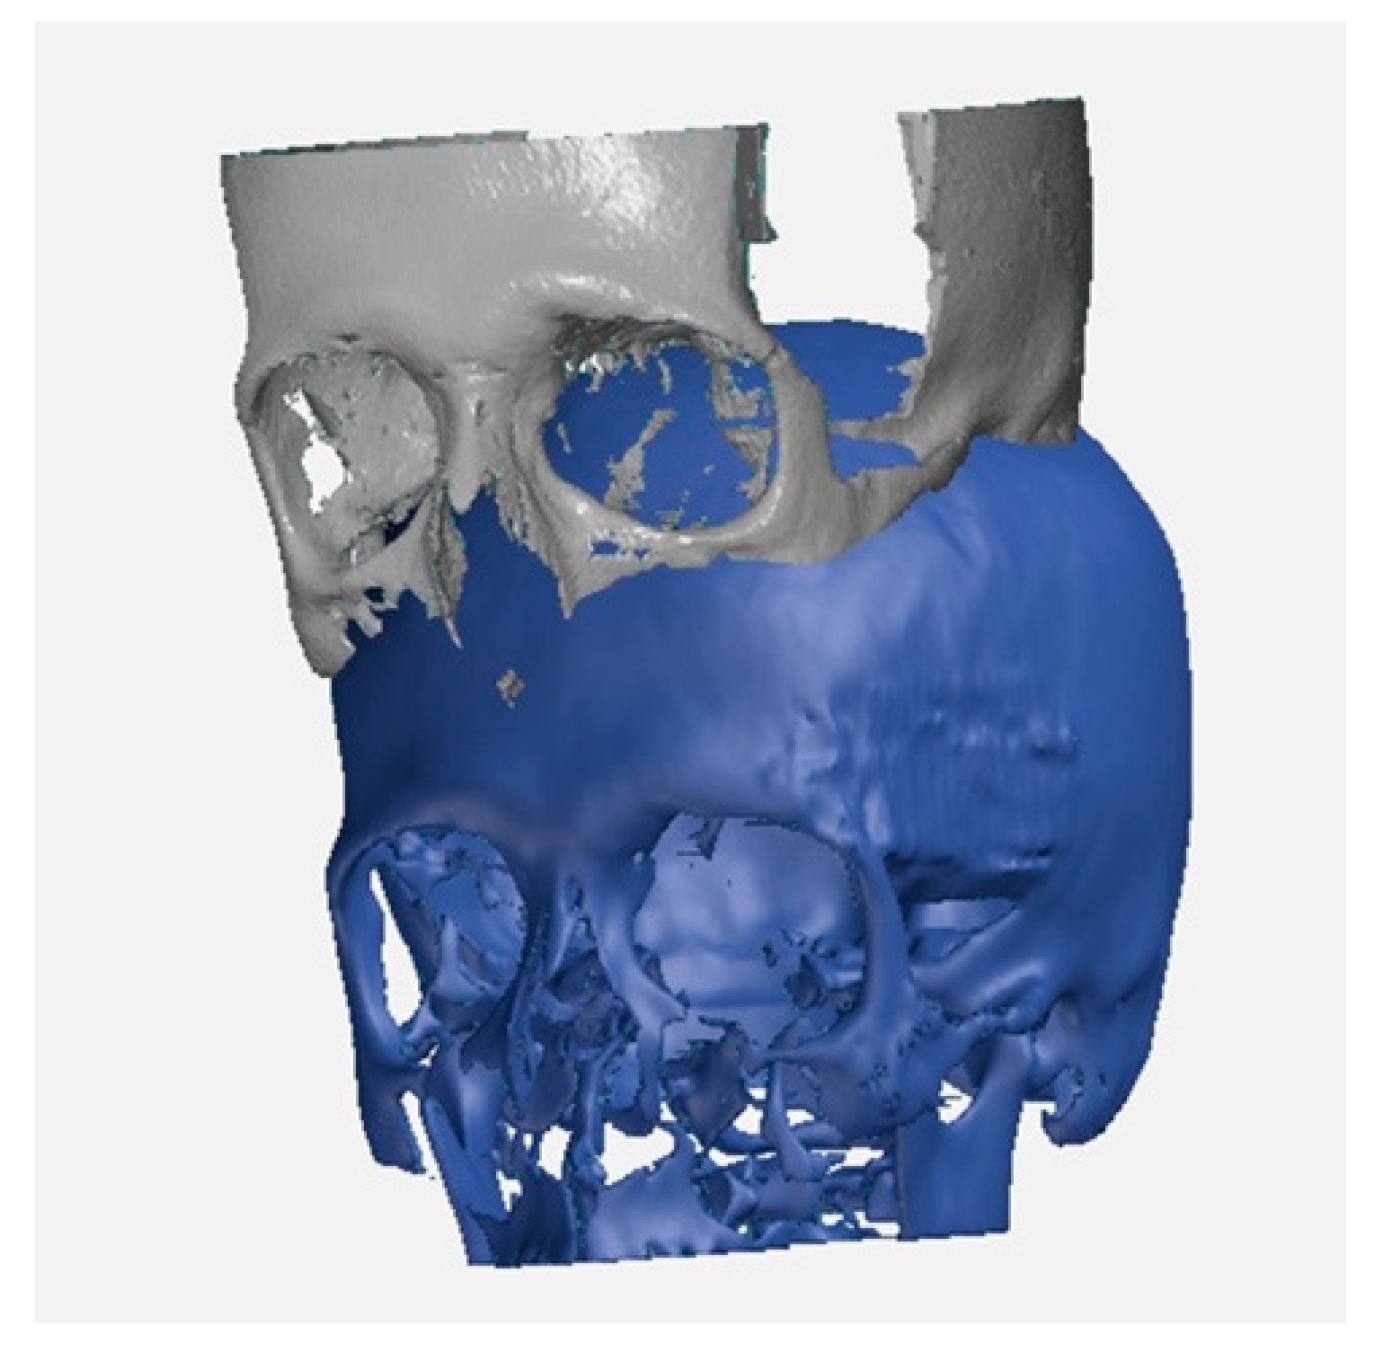

Once models reproduce the patient’s anatomy faithfully, it is possible to import the two geometric models into GOM Inspect to measure the differences between them. This image matching has to be done on images taken before the surgery versus those taken at least six months after when the patient is undergoing a control CT: Such timeframe allows seeing the beginning of the remodeling process supported by SB [29]. Moreover, this step overlap is necessary to get a comparison between the two models. The reference system of one model is converted into the reference system of the other model, to get a correct overlapping and avoid errors. It is very important to have a perfect alignment of the measuring model to the nominal model. Figure 2 shows an example of the pre-operative model imported as a mesh file (in gray) and the post-operative template imported as a CAD body file (in blue).

Figure 2.

Example of the pre-operative model imported as a mesh file (in gray) and the post-operative template imported as a CAD body file (in blue).